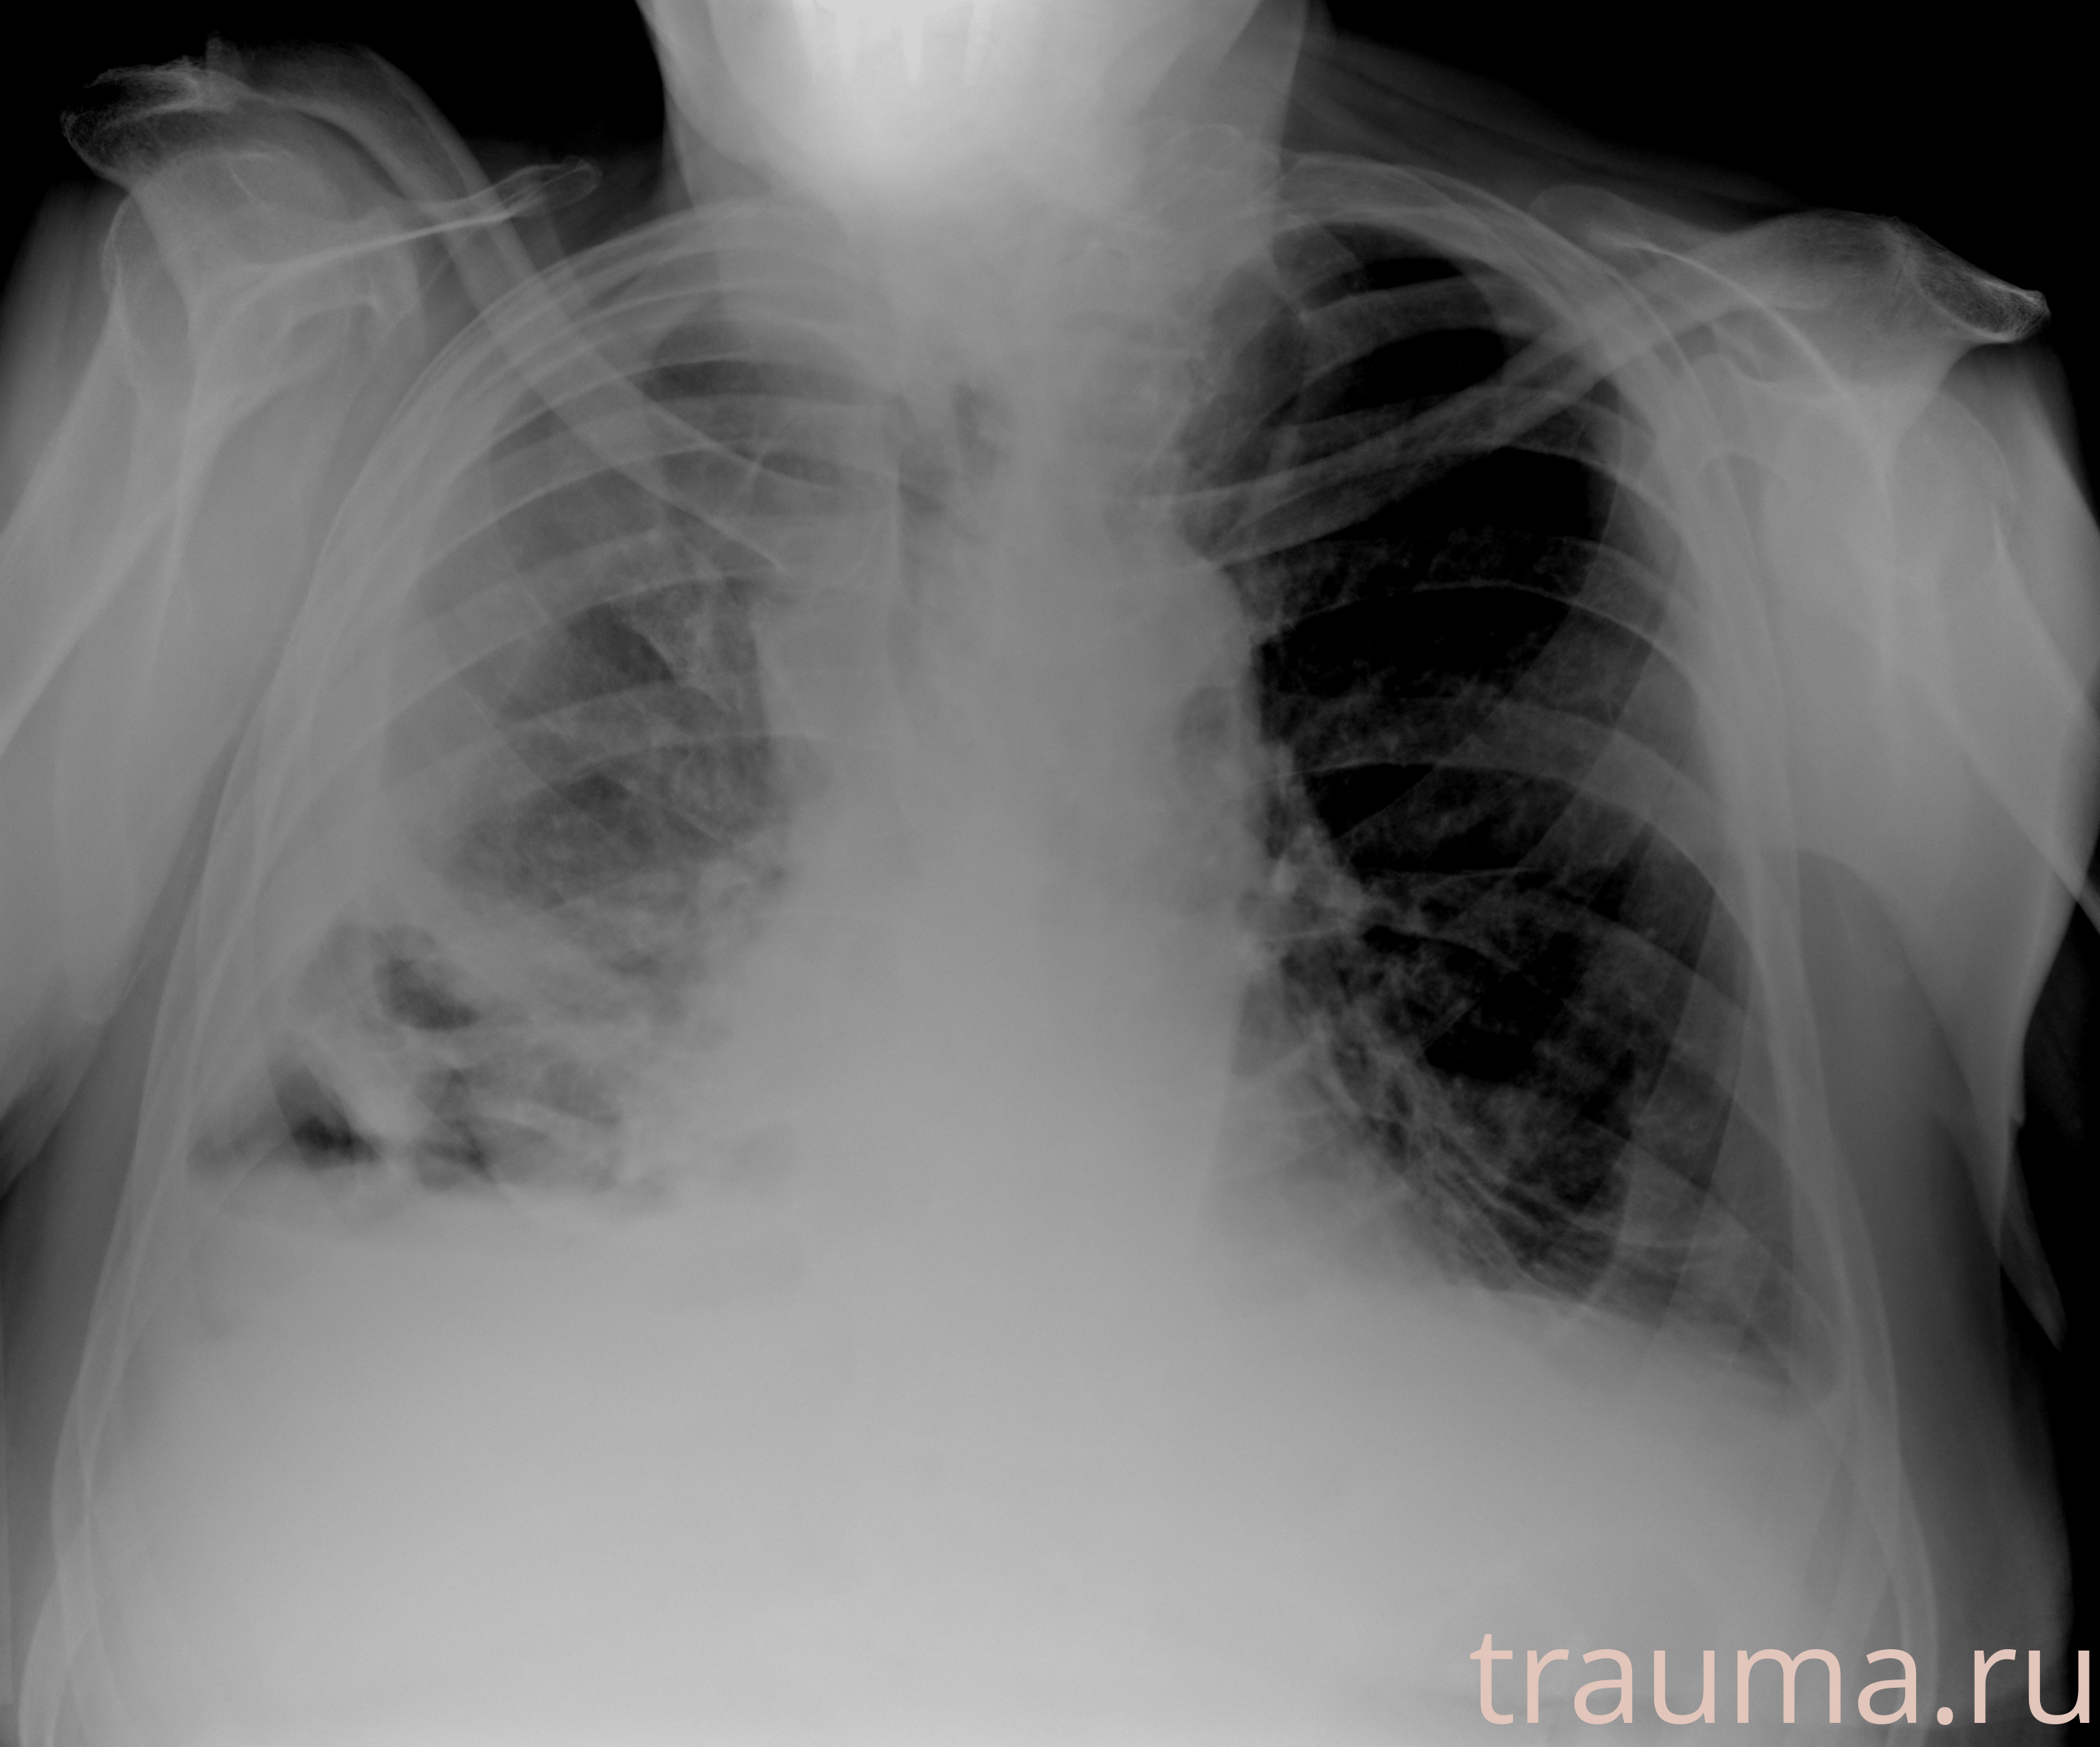

Рентген на дому: по вашему адресу приезжает врач-рентгенолог, травматолог-ортопед с мобильным рентгеновским аппаратом, проводит диагностику травмы или заболевания, делает необходимые рентгенограммы, дает рекомендации по дальнейшему лечению. Получить качественные снимки в домашних условиях возможно благодаря уникальной методике, разработанной МосРентген Центром для института  Склифосовского